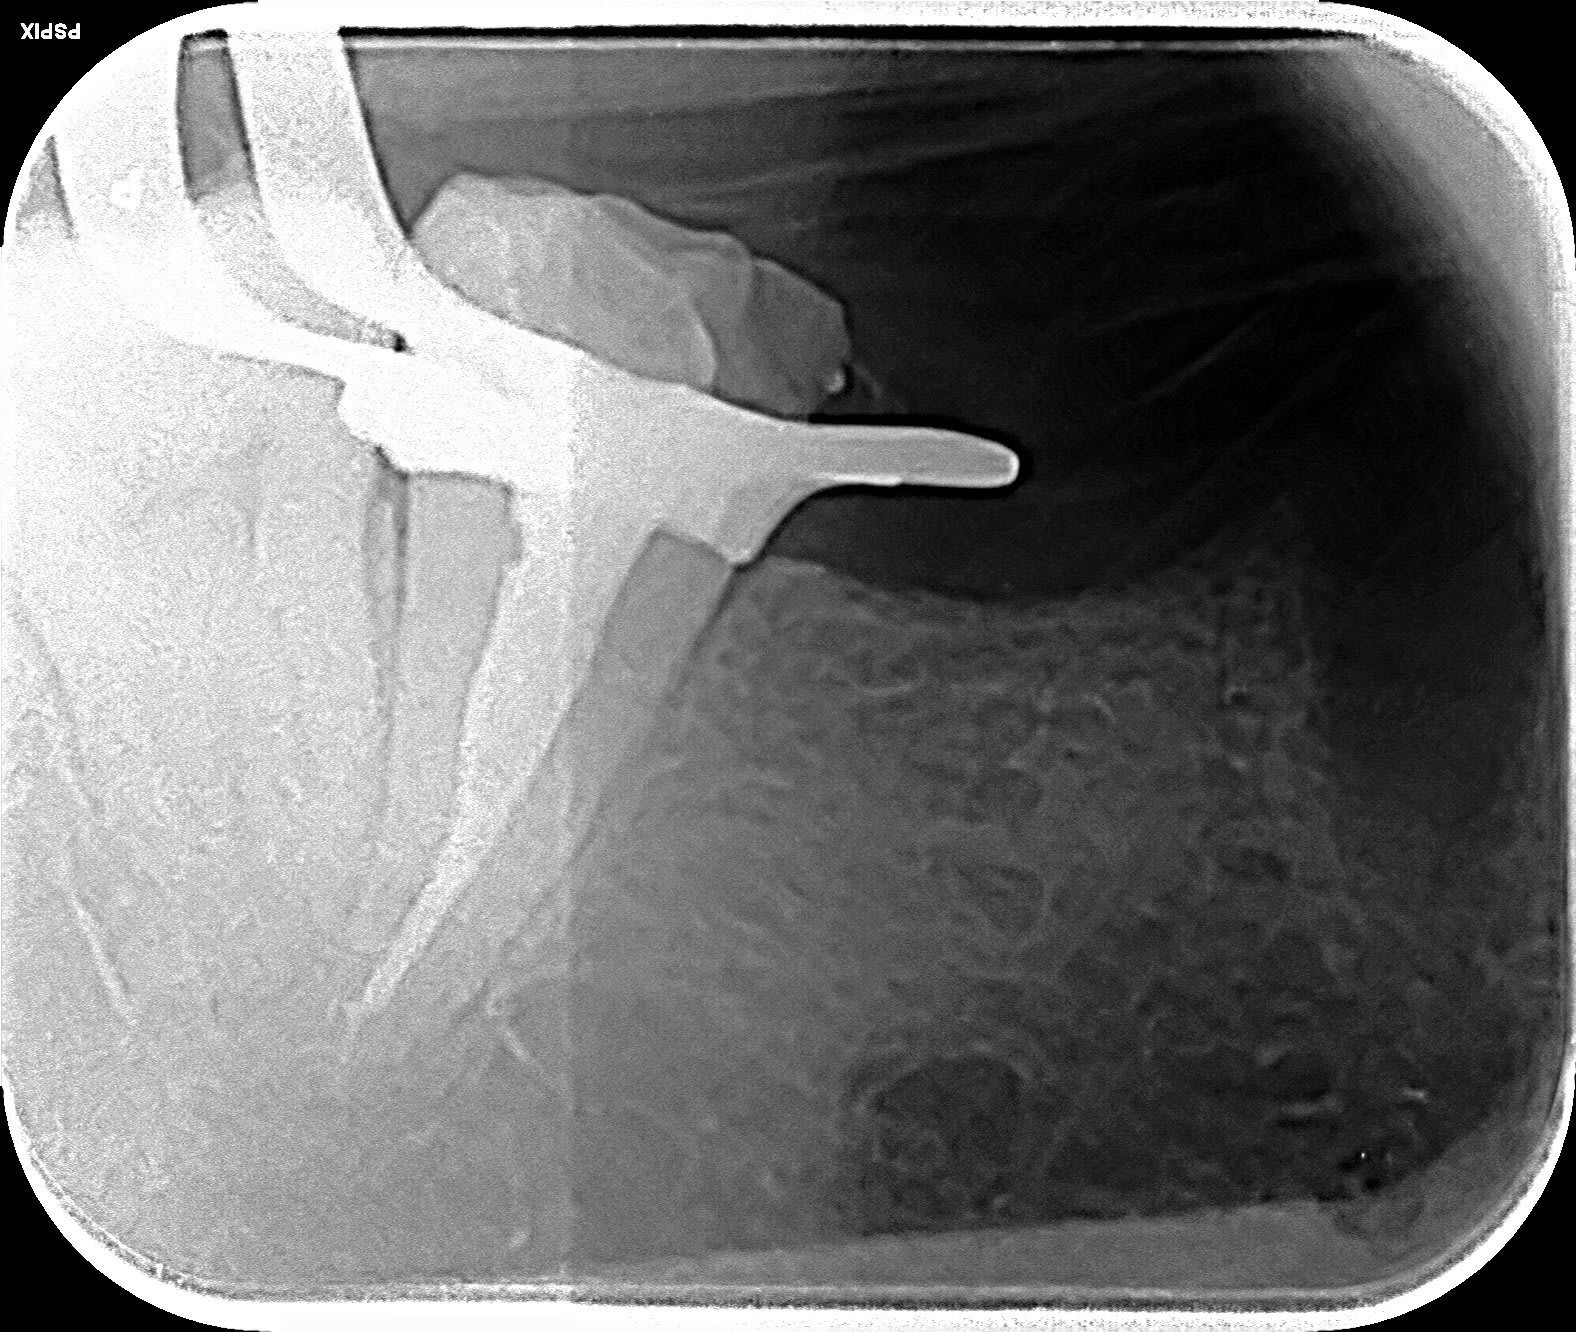

tronculaire... qualité radio pas top:-(

Injection, le temps de sortir le matos des sachets, c'était pris... merkiki ? le tendon profond 😉

Endo 37 bis isphmz - Eugenol

Endo 37 reyf7u - Eugenol